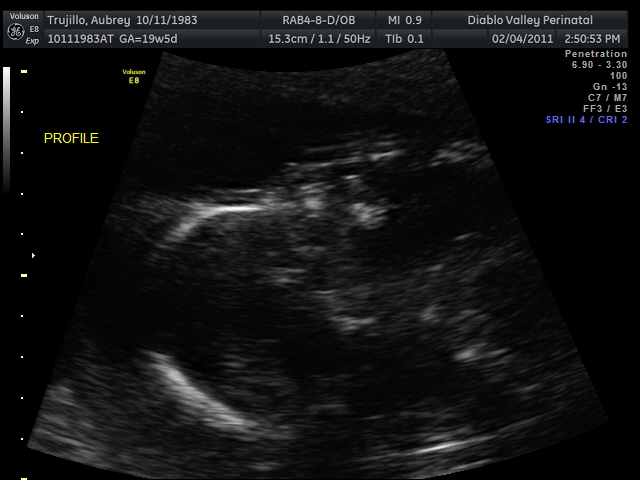

20 weeks - profile20 weeks - Profile again20 weeks - Right foot!20 weeks - sucking thumb!!!!20 weeks - hand near face20 weeks - flexing his bony arms!20 weeks - hiding from mommy and daddy!20 weeks - it's a boy!33 weeks - 3D!33 weeks - 3D!33 weeks - 3D!